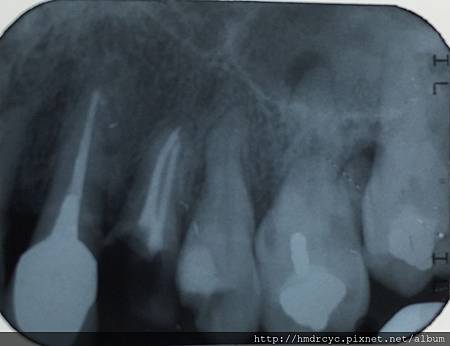

照張X光片檢查很重要

但只要牙肉下的牙根還沒有斷裂

經過X光評估建議先裝鑄心恢復